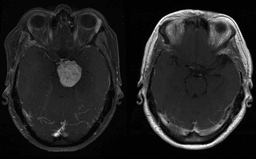

- Contrast agents are commonly used for X-rays and CT's to better characterize disease, but contrast doesn't work with MRI. That's where the element Gadolinium comes into play.

- Gadolinium is toxic alone, but when paired with chelators it can be used in humans and allows for better characterization of tumors or abnormal tissue on MRI.

- It helps identify this abnormal tissue because when MRI causes polarization of our body's cells, the gadolinium, which has the maximum number of unpaired electrons in its orbital shells, alters the rate of decay in abnormal tissue highlighting abnormalities on imaging.